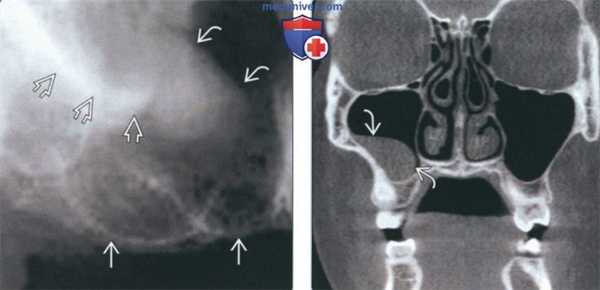

(Слева) На аксиальной КТ в костном окне определяется мукоцеле задних ячеек решетчатой пазухи, распространяющееся в сфеноидальные пазухи, но не в глазницу. Костная пластинка на периферии мукоцеле истончена и видоизменена.

(Справа) На корональной КТ в костном окне в правой верхнечелюстной пазухе (нетипичная локализация) определяется мукоцеле большого размера, приводящее к обструкции полоаи носа. Обратите внимание на признаки хронического левоаороннего гайморита: уменьшение объема пазухи и утолщение ее стенок.